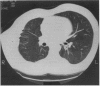

The lungs of 50 symptom free workers exposed to amosite and with normal pulmonary function tests were examined by high resolution computed tomography (HRCT). Twenty five had normal standard chest radiographs whereas the other 25 had radiographs interpreted as near normal (International Labour Office profusion score < 0/1 or suspected pleural plaques). In 13 of the workers the results of HRCT were negative; in 22 pleural plaques were found, in five there was only parenchymal involvement, and 10 had both pleural and parenchymal changes. The mean duration of exposure to amosite was significantly longer for the subjects with parenchymal signs than for those with normal parenchyma and for the workers with pleural plaques than for those with normal pleura and lung parenchyma. The prevalence of identified pleural and parenchymal abnormalities in the 50 workers was also significantly higher than in a reference group without exposure to asbestos. It is concluded that HRCT may detect initial lung and pleural involvement in symptom free workers exposed to amosite and the mean duration of exposure is longer for subjects with parenchymal or pleural involvement.